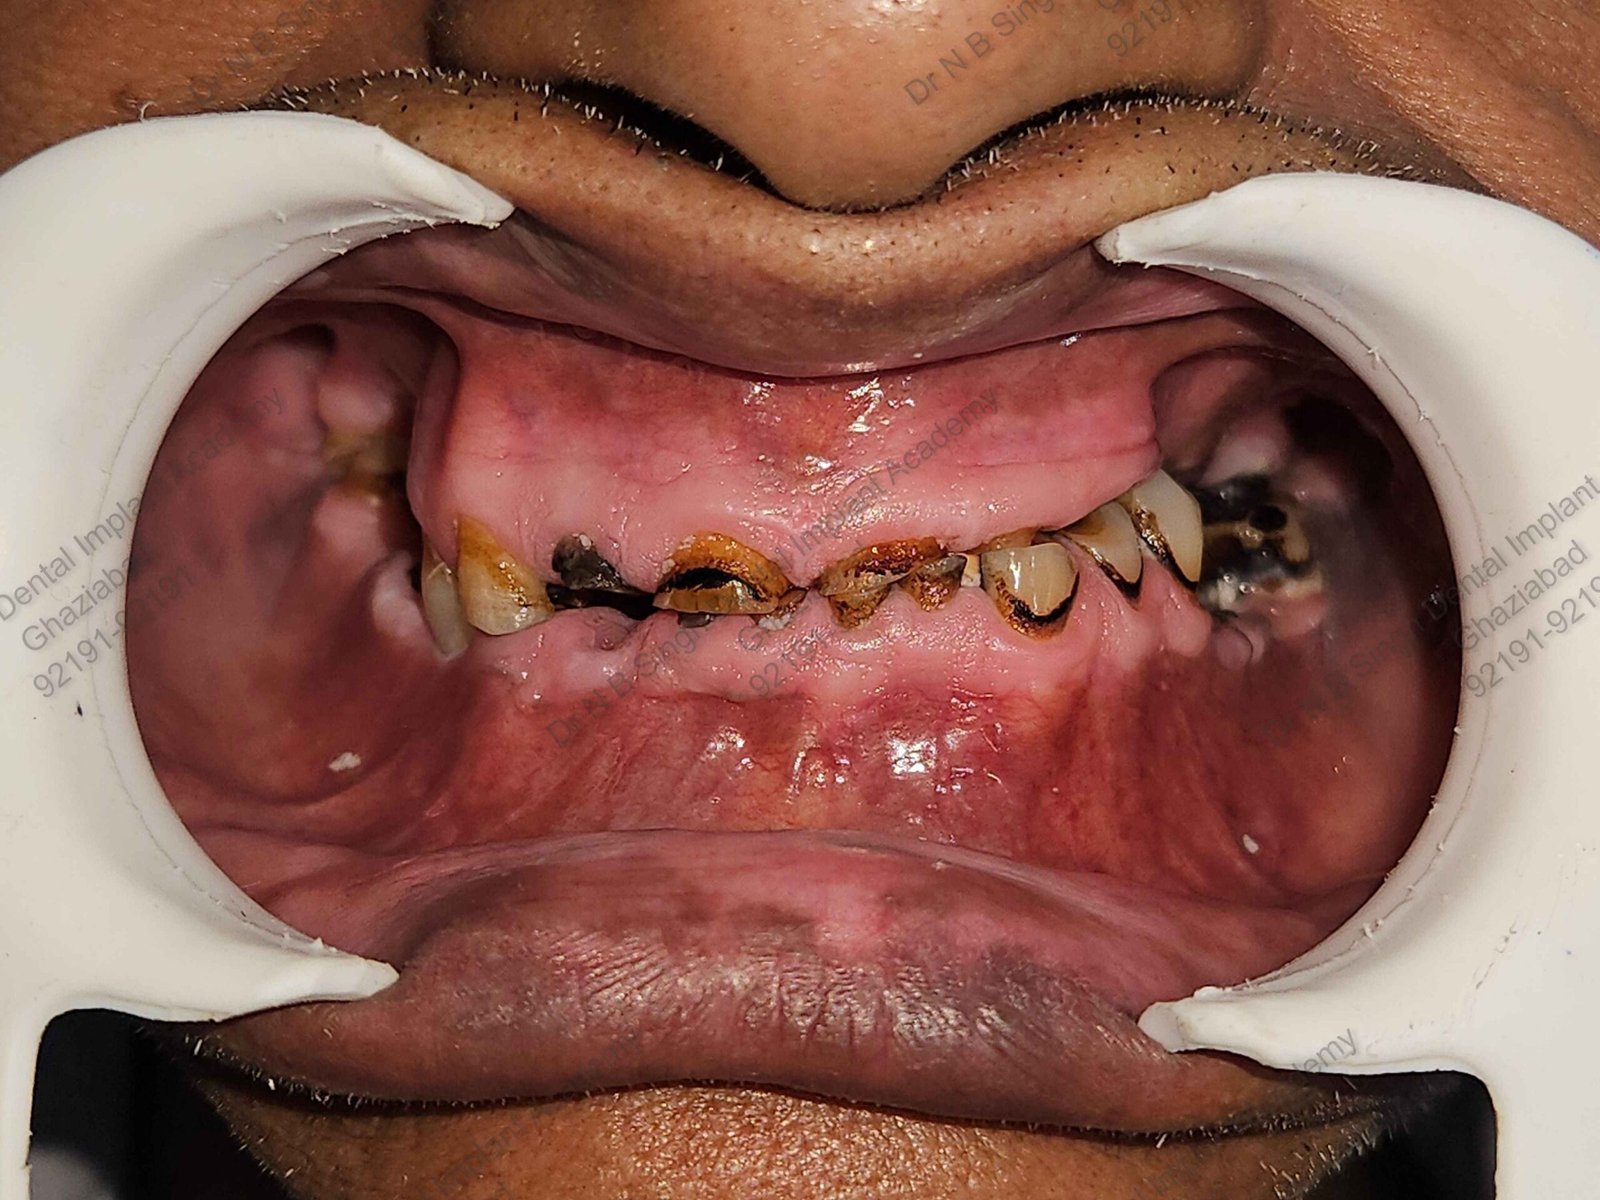

C1005 zygomatic basal implant full mouth – Ali Hasan 4

Dr. N.B. Singh